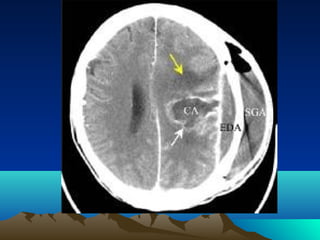

•CT scan

•MRI

Complicatio

• Herniation

n

• Rupture to ventricle & SAS